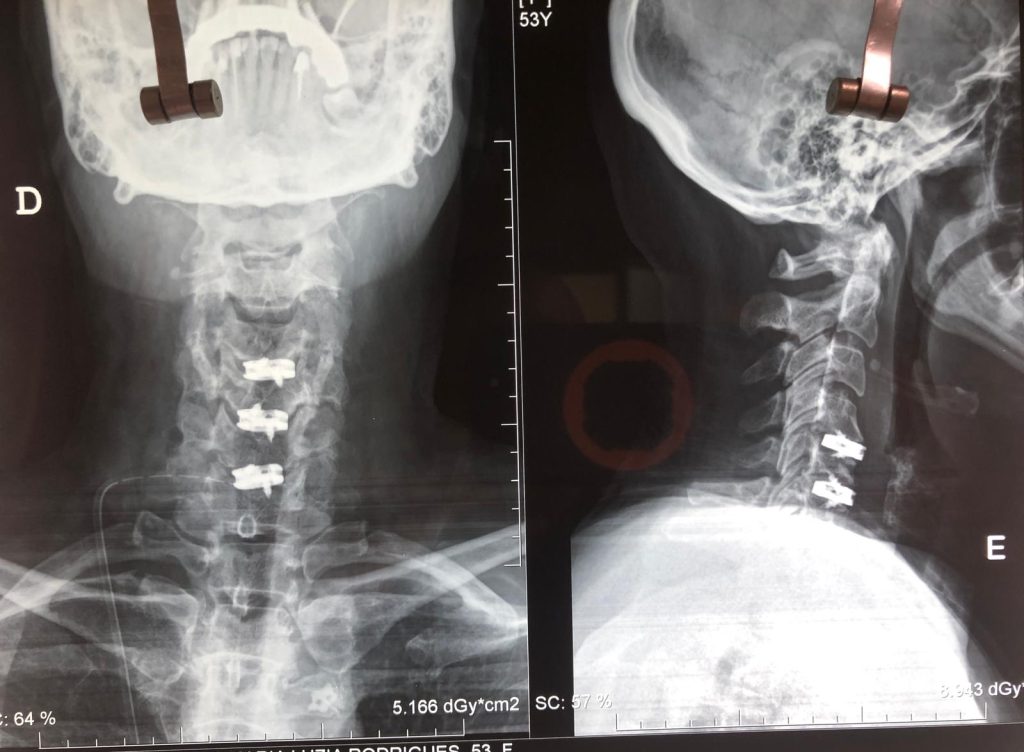

Imagem 1 – Hérnia cervical em três níveis (pós-operatório)

Radiografia da coluna cervical em incidência ântero-posterior e lateral, mostrando a colocação de três cages cervicais fixas com parafusos nos níveis C4–C5, C5–C6 e C6–C7, assegurando a estabilização da coluna após a intervenção cirúrgica.